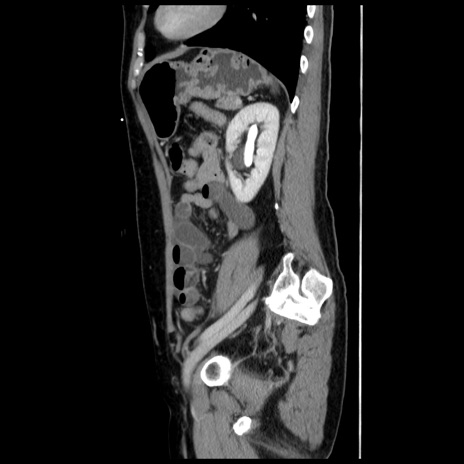

冠状断像

【症例】 50歳代女性

【主訴】 腹痛

【現病歴】前日生レバーを食べた。今朝に排便あり。 昼前に突然発症の腹痛を生じ、当院救急外来を受診した。

【既往歴】 子宮筋腫にてで子宮全摘後

【身体所見】 意識清明、腹部:平坦、軟、下腹部やや左を中心に圧痛・反跳痛あり、筋性防御あり

【データ】WBC 7800、CRP 0.07